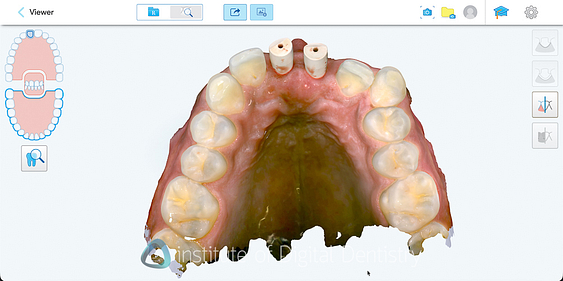

Beyond dimensional accuracy, my favorite part of the Lumina is the scan textures and quality. It produces exceptional final scans. These are the nicest I have seen on the market.

The photorealistic textures are simply unmatched by any other scanner currently available in terms of detail, resolution, and colors. These visuals offer both clinical and communication advantages, and they work well within the extensive range of patient communication apps available within the Align Oral Health Suite.

These scan images really are nice to look at, even for patients. I mean, the detail capture is market-leading, with the scanning picking up even the twists on a ligature tie (see the images below). Gingival texture, tooth characteristics, and restoration details appear with clarity that approaches the quality of intraoral photography. It really is incredible tech.